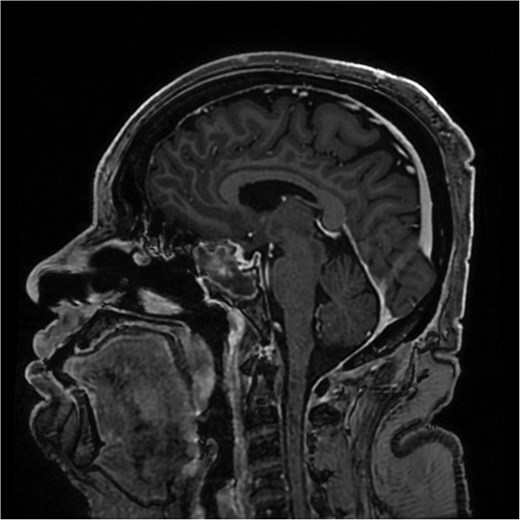

A sagittal brain MRI reveals the same mass with superior extension to the sellar and suprasellar regions. The lesion is exerting a compression to the optic chiasm. The mass effect extends posteriorly toward the clivus, with irregular margins indicating invasive potential. Adjacent structures like the pituitary stalk appear to be displaced.

Despite treatment with cabergoline, follow-up prolactin level remained elevated, and imaging showed a growing tumor size. Clinically, the patient's symptoms persisted, with worsening headaches. Afterward, her prolactin level had dramatically risen to 2000 ng/ml. She was admitted with daily severe headaches, abdominal pain, vomiting, and oral intake intolerance. A brain MRI demonstrated an enlarged sellar and suprasellar mass measuring 3.2 × 1.7 × 3.0 cm, compressing the optic chiasm. Additionally, her prolactin level diminished to 2.7 ng/ml, raising concern of a growing pituitary macroadenoma.

She underwent endoscopic trans-sphenoidal debulking of the suprasellar lesion (Figs 3 and 4). Postoperatively, the patient developed complications, including diabetes insipidus and panhypopituitarism, requiring levothyroxine and corticosteroid replacement therapy. Histopathology revealed a diagnosis of high-grade primary central nervous system (CNS) B-cell lymphoma. Microscopic analysis showed sheets of atypical lymphoid cells with high mitotic activity. Consequently, the patient was initiated on rituximab and high-dose methotrexate (HD-MTX). Nevertheless, methotrexate was terminated due to the onset of acute kidney injury. Given the patient's intolerance to further HD-MTX, nivolumab was commenced based on PD-L1 expression. While there was partial symptom relief, the tumor response was inadequate. Therefore, the patient underwent whole-brain radiotherapy with a boost to the pituitary region, receiving a total dose of 45 Gy over 25 fractions. This treatment was effective, though she experienced alopecia, mild nausea, blurred vision, headaches, and severe vulvar itching.